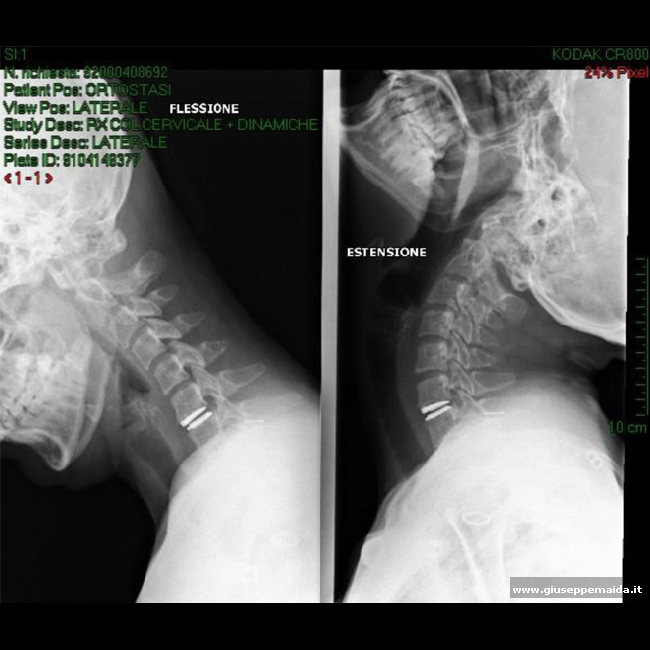

In alcuni casi selezionati è possibile,rimosso microchirurgicamente il disco intervertebrale patologico (ed erniato),sostituire lo stesso disco con un disco "meccanico" artificiale,in modo da preservare il movimento delle vertebre: alcuni esempi.